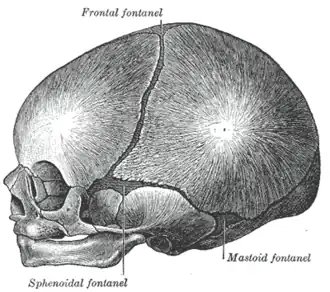

The skull at birth, showing the lateral fontanelle.

The skull at birth, showing the lateral fontanelle. -

Coronal suture of new born baby.

Coronal suture of new born baby.